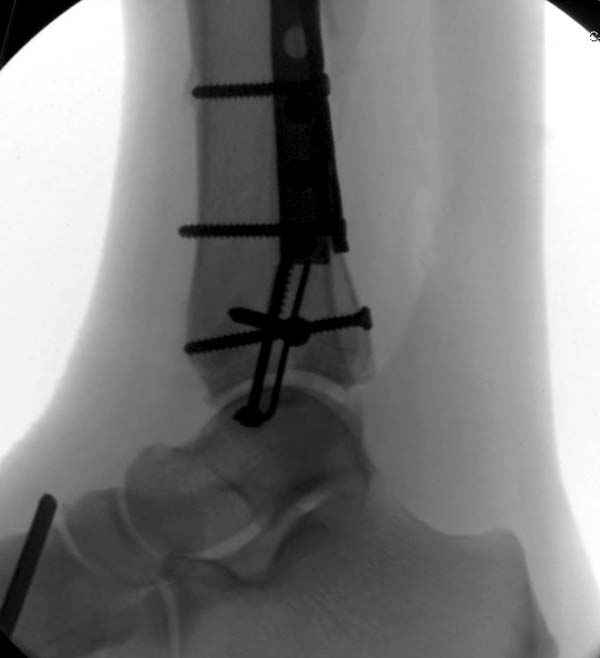

По снимкам довольно сохранный сустав, и такой сустав желательно попытаться восстановить всеми возможными мерами.

Артродез штифтом от Синтеза - немного агрессивно, а для улучшения качества жизни вместо артродеза голеностопа можно было бы предложить артродез подтаранного сустава. Тремя 6.5 мм каннюлированными шурупами через пятку.

Насчет пилона, прошло достаточное время для консолидации и прекрасная возможность для демонстрации, что такие случаи могут быть успешно вылечены остеотомией, несмотря на засторелость.

Из заднего доступа остеотомия тонким остеотомом и коррекции на ЭОПе.

Без применения сложной конструкции, а обычными параллельными шурупами. Шурупы в 3.5 мм и дополнительно фиксация крючковидной пластиной, сделанной из 3.5 mm semitubular пластиной, Butress или аntiglade фиксация.

Здесь алгоритм фиксации свежего перелома и преоперационный план для обсуждаемого случая.